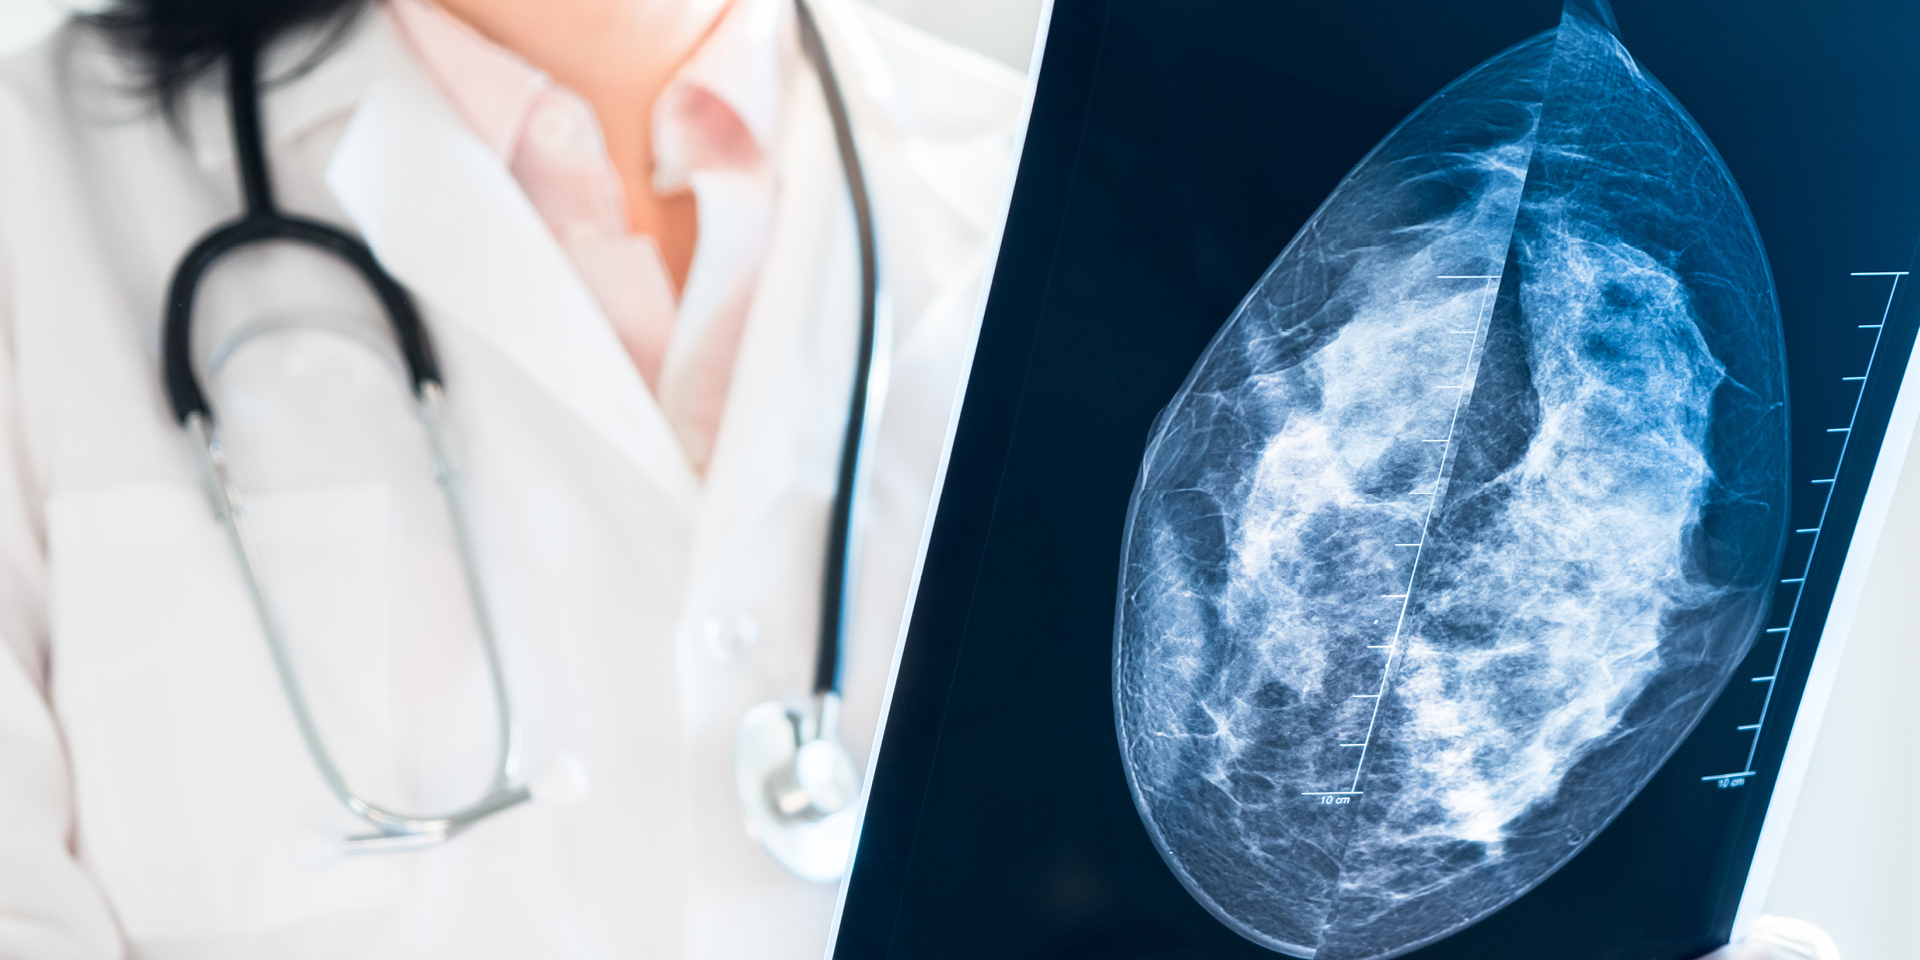

Doctor holding mammography film

Doylestown Health offers an advanced technology that gives physicians unprecedented views of the breast and may aid in the early detection of breast cancer, particularly for patients with dense breasts. This imaging service is called 3D mammography or breast tomosynthesis.

Unlike digital mammography, which produces a 2-dimensional image of the breast, 3D mammography creates a series of images that allows the radiologist to view the breast in multiple, connected slices. This process is similar to how a computed tomography (CT) scanner produces images of various structures inside the body.